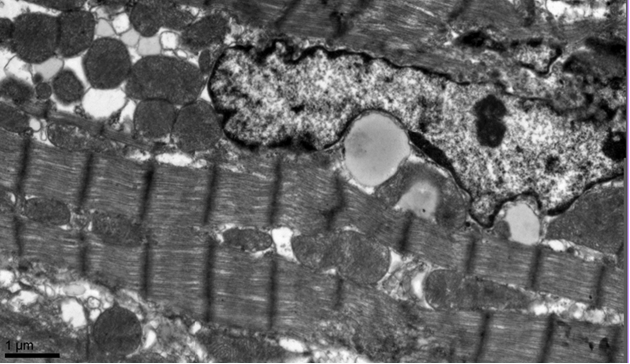

Electron-microscopic

analysis revealed the nucleus of Japanese quail’s cardiomyocyte is situated in

center and has elongate form and invaginated borders. The main part of

cytoplasm (up to 70%) is occupied by myofibrils that organized in parallel

rows. In old quails’ cardiomyocytes this type of myofibrils’ organization is

sometimes damaged. From 9 to 52 weeks of life myofibrils volume is significantly

decreased. However, the particular zones where contractile apparatus is

hypertrophied can be seen in cells of old birds.

Picture 1. Cardiomyocyte of 9 weeks old

Japanese quail

Mitochondria

are localized between myofibrilar rows and in perinuclear region; their volume

is 30% of cytoplasm at the average. The mitochondria’s volume is significantly increased

in the cells of 52 weeks old birds. So, the mitochondria/myofibrils ratio is

shifted to mitochondria in old birds’ heart, comparing with younger ones.